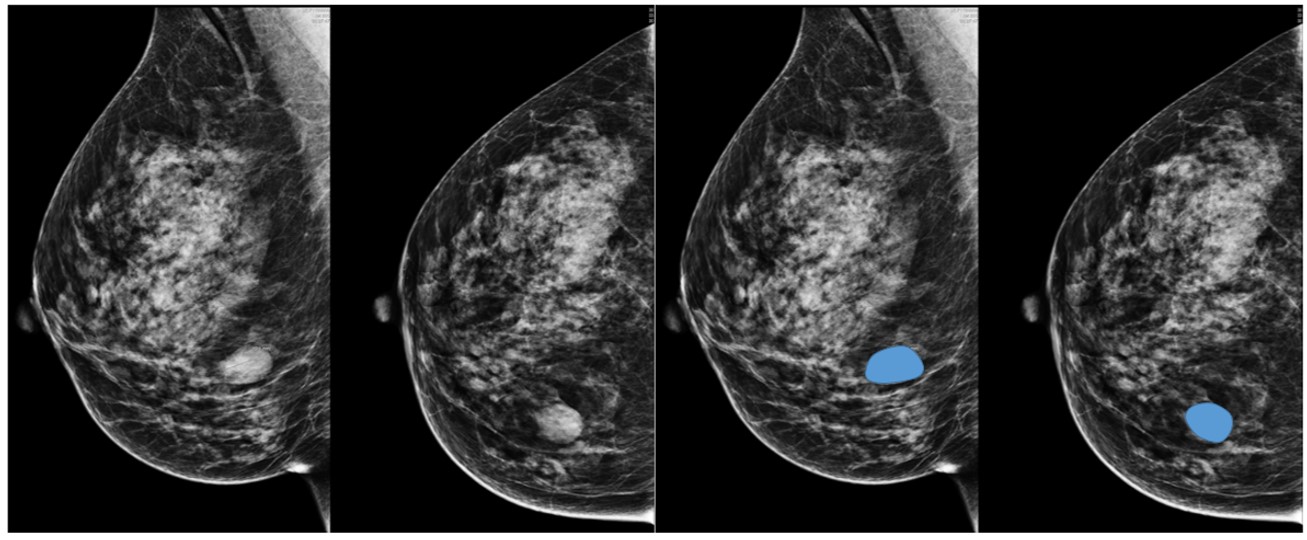

Фкм birads

Фкм birads 83 фотографий